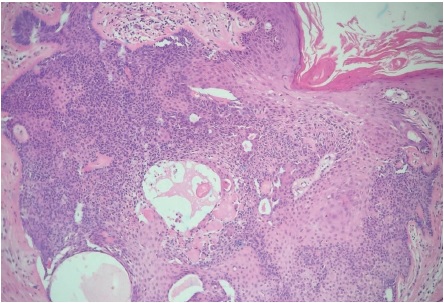

Paciente do sexo feminino, 65 anos, parda, queixando-se de prurido no couro cabeludo há um mês. Ao exame observava-se na região occipital: placa verrucosa, discretamente eritematosa medindo cerca de 2,5cm no seu maior eixo (Figuras 1 e 2). Segundo a paciente, desde o nascimento apresentava lesão assintomática no couro cabeludo que, há um mês, tornara-se pruriginosa. Optou-se por biópsia incisional da lesão e exame histopatológico, o qual evidenciou carcinoma basocelular nodular (Figura 3). Realizada então a excisão completa da lesão com margem, cujo exame histopatológico revelou: nevo sebáceo associado a siringocistoadenoma papilífero, adenoma tubular apócrino, triquilemoma (Figuras 4 a 7) e fibrose dérmica cicatricial.

O NSJ, conhecido também como nevo organoide, é mais incidente no couro cabeludo, podendo apresentar-se na face e menos comumente nos membros.3,5 Ocorre em aproximadamente 0,3% dos indivíduos, sem predileção por gênero. A lesão em geral está presente ao nascimento e apresenta-se como placa bem delimitada constituída por múltiplas pápulas confluentes de coloração amarelo-alaranjada ou amarelo-acastanhada, predominantemente no couro cabeludo, onde cursa com alopecia no local da lesão.3 Apresenta distribuição bimodal: durante a puberdade, quando sua superfície torna-se espessada e verrucosa por estímulos hormonais aos componentes écrinos e apócrinos, podendo, na fase adulta, a lesão se tornar nodular com a ocorrência de ulcerações e crostas. A possibilidade de surgimento de neoplasias secundárias nessa fase varia de dez a 30%, sendo as principais o carcinoma basocelular, o siringocistoadenoma papilífero (ambos observados nessa paciente) e o tricoblastoma.3

Outros tumores já descritos em associação com o NSJ incluem: benignos - triquilemoma (também presente nessa paciente), tricoadenoma, hidroadenoma nodular, hidrocistoma apócrino, siringoma, nevo apócrino, poroma, espiradenoma, queratoacantoma, piloleiomioma, osteoma, nevo melanocítico, queratose seborreica e queratoacantoma;4,6-8 malignos - carcinoma espinocelular, carcinoma sebáceo, carcinoma apócrino, leiomiossarcoma, porocarcinoma écrino e melanoma.6,9